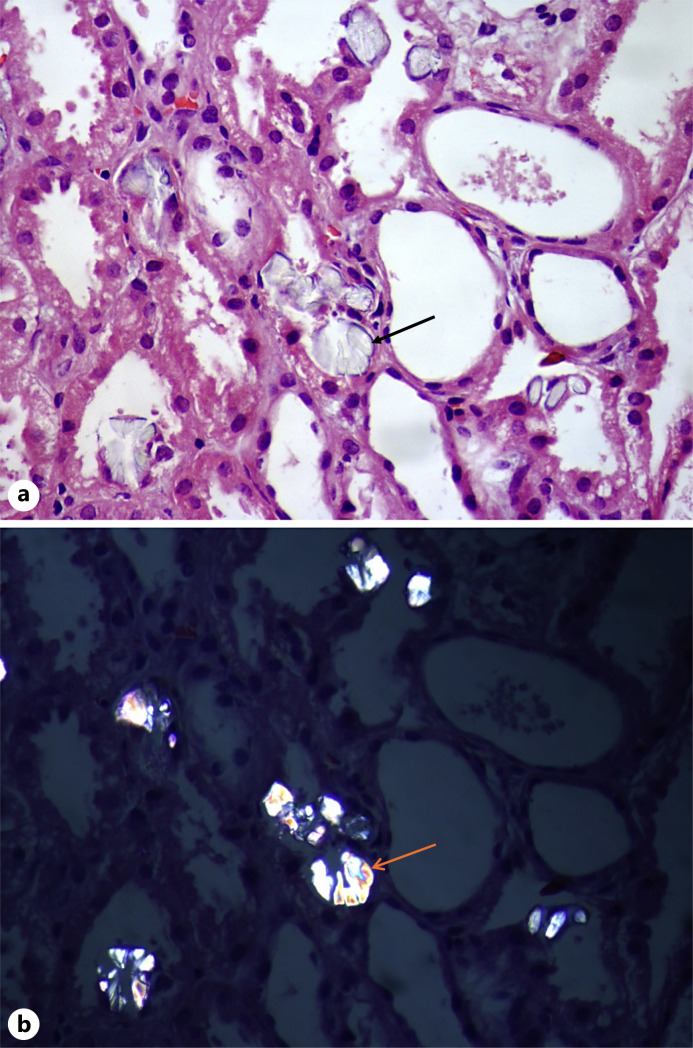

Case presentations: This case series comprises 4 patients exhibiting varied renal presentations linked to herbal medication usage. Notably, oxalate nephropathy emerged as a predominant finding. Through comprehensive clinical assessments and renal biopsies, we elucidated the pathophysiological mechanisms underlying herbal nephrotoxicity. Timely recognition and discontinuation of the offending herb, alongside tailored therapeutic interventions like corticosteroid administration, facilitated favourable patient outcomes.